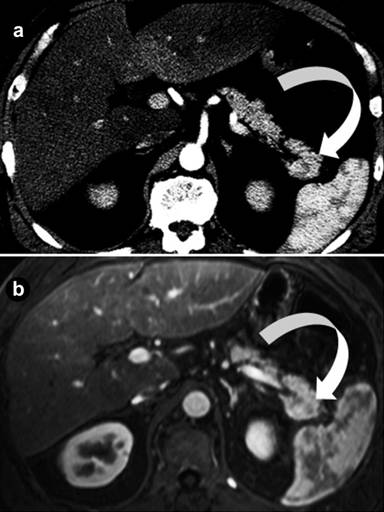

The differential diagnoses for a small solitary soft tissue mass in the pancreatic tail include intrapancreatic accessory spleen, pancreatic adenocarcinoma, neuroendocrine tumor and pancreatic metastases. These lesions can often be characterized and differentiated on imaging (Table 1). High resolution multiphasic contrast enhanced-CT and/or MRI, widely available in most centers worldwide, can render precise lesion characterization and differentiation. When compared to the spleen, intrapancreatic accessory spleen exhibits a similar attenuation and signal intensity on CT and MRI, respectively, and similar post-contrast enhancement (throughout all vascular phases) [4]. In particular, the arciform pattern of arterial enhancement within the intrapancreatic accessory spleen, similar to that seen in the adjacent spleen, is highly suggestive of the diagnosis (Figure 1) [4]. The arciform pattern of arterial enhancement is secondary to perfusion differences between red pulp and white pulp present within tissues of splenic origin. This arciform enhancement helps to differentiate intrapancreatic accessory spleen from other focal arterially enhancing pathologies in the pancreatic tail such as neuroendocrine tumor (heterogeneous or ring-like arterial enhancement) and pancreatic metastases (heterogeneous arterial enhancement) from hypervascular neoplasms such as renal cell carcinoma. Solid pseudopapillary tumor may show mild heterogeneous arterial enhancement but it is not typically confused with intrapancreatic accessory spleen as it is generally large at presentation (mean size of 9 cm) [4]. Pancreatic adenocarcinoma is a hypovascular neoplasm. In indeterminate cases, specialist tests such as a 99mTechnetium-heat damaged red blood cell (99mT-HDRBC) study, a 99mT-sufur colloid study or a superparamagnetic iron oxide (SPIO) enhanced MRI study may confirm the diagnosis [4, 5]. Intrapancreatic accessory spleen may show high radiotracer uptake on 99mT-HDRBC and 99mT-sufur colloid and sensitivity may be improved if these tests are performed as part of a single photon emission computed tomography (SPECT) examination. On superparamagnetic iron oxide enhanced MRI, intrapancreatic accessory spleen exhibits signal loss similar to the spleen on T2/T2*-weighted MR images due to phagocytosis by reticuloendothelial cells in these tissues [4, 5]. Limitations include small intrapancreatic accessory spleen foci that do not contain sufficient reticuloendothelial tissue to render confident imaging characterization and the specialist nature of these tests (e.g., superparamagnetic iron oxide MRI contrast agents are not routinely performed clinically) which precludes widespread accessibility and uptake. Contrast enhanced ultrasound has also been advocated as a diagnostic test for evaluating intrapancreatic accessory spleen [6]. However, this technique is limited by difficulties in obtaining adequate sonographic visualization of this small deep seated lesion; and image obscuration from overlying bowel gas shadowing. Furthermore, not all centers perform contrast enhanced ultrasound. When non-invasive diagnostic tests fail, fine needle aspiration biopsy employing image guidance (e.g., CT, ultrasound, endoscopic ultrasound) can be performed for cytological diagnosis [1]. However, this is not a full proof procedure and may yield unsatisfactory results due inadequate biopsy specimens and sampling error. The small size of intrapancreatic accessory spleen and deep location make it a challenging target to both access and biopsy. Furthermore, there is a small risk of biopsy related complications such as hematoma, pancreatitis and trauma to adjacent tissues. It is highly preferable if diagnosis can be made non-invasively, whenever possible.

Figure 1. A 59-year-old male with a previous history of a resected duodenal carcinoid tumor. a. .An axial arterial-phase contrast enhanced CT image. b. An axial arterial-phase contrast enhanced MRI image. Arciform arterial enhancement, similar to that found in the spleen, is present in the intrapancreatic accessory spleen (IPAS) (curved arrows) on both the CT and MRI images. The IPAS showed high radiotracer uptake on a corresponding 99mTechnetium heat damaged red blood cell study and remained stable on a follow up MRI examination performed at 12 months. |